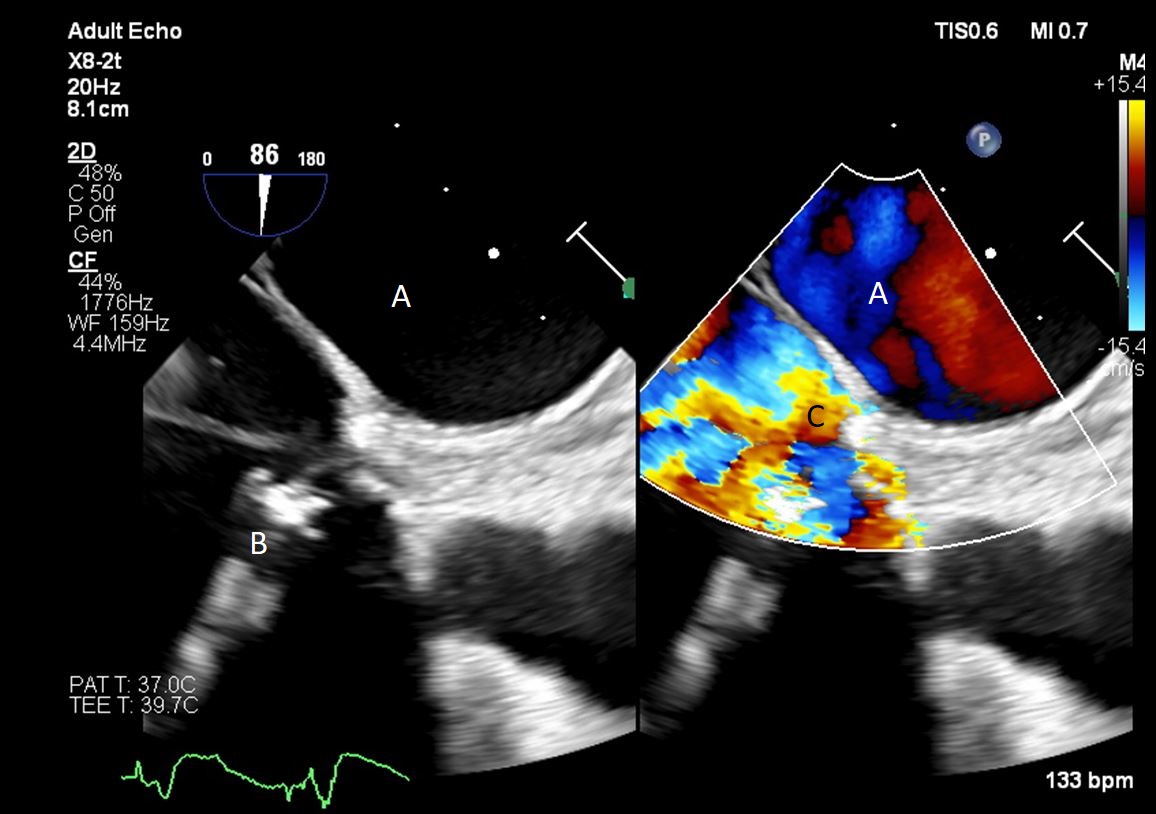

Fig. 4.Impella (A) placement causing disruption and damage to subvalvular apparatus resulting in mitral valve flail (B) and mitral regurgitation (C).

Both TTE and TEE can help with ideal positioning of the Impella (Figs. 5,6). The distance from the aortic valve to the Impella inlet should be measured. This should ideally be 3.5–4 cm for all Impella devices except for the Impella 5.5 for which it is 5 cm [15] (Fig. 7). The outlet should be 1.5–2 cm above the sinuses of Valsalva. The catheter should be angled towards the LV apex and away from the septum and mitral valve. The positioning of both the inlet in the LV cavity and the outlet above the aortic valve should be confirmed. Color flow doppler imaging can help confirm this positioning as a mosaic pattern will be visualized near the inlet and outlet ports on spectral doppler (Fig. 8). Real-time 3D echocardiography can also be used to help in visualizing Impella positioning relative to other anatomical structures (Fig. 9). After placement of the Impella, the aortic and mitral valves should be interrogated for any new or worsening regurgitation or dysfunction [16]. TEE can also help identify additional complications of Impella placement including pericardial effusion or LV free wall rupture [17].